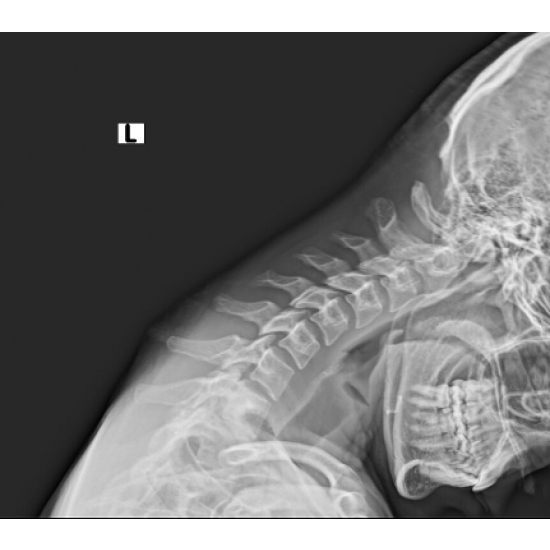

XR 4+ view cervical spine: Normal vertebral body and disc height. No acute osseous abnormality. Case Photo #1 , Case Photo #2 , Case Photo #3 , Case Photo #4